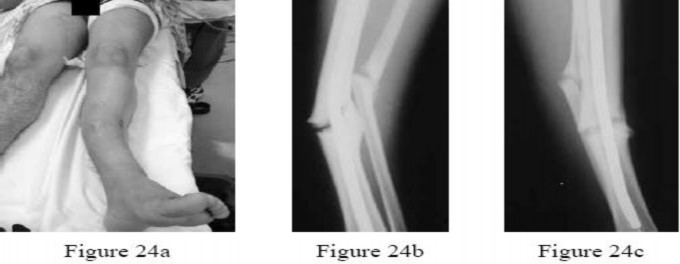

A 19-year-old man underwent intramedullary nailing of a closed tibia fracture 1 year ago and has never been pain free. While playing football, he was tackled and sustained the injury shown in Figure 24a.What is the best treatment option based on the radiographs seen in Figures 24b and 24c?